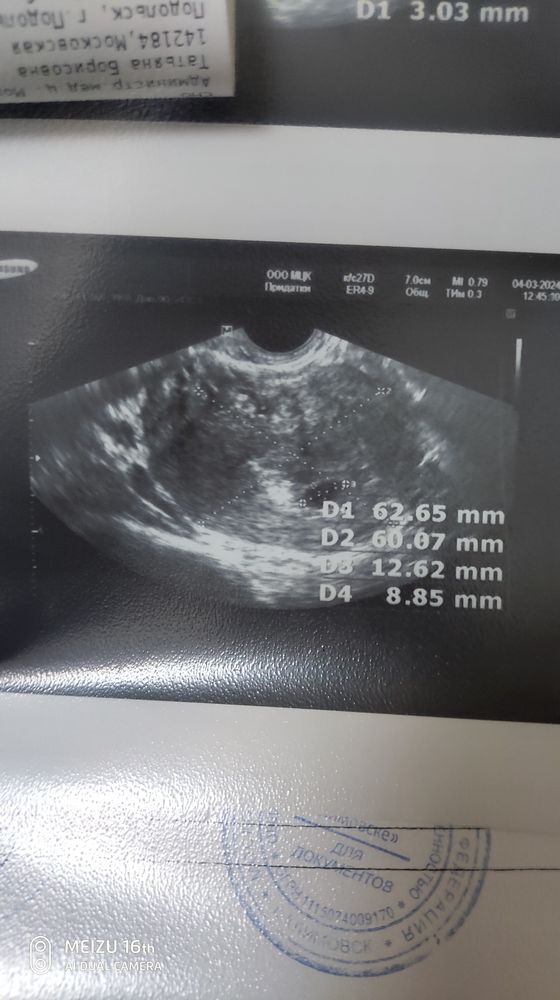

Затрудняюсь с категориейДобрый день. Была неделю назад на УЗИ. 5.2 по М. ПЯ 7 мм ни эмбриона, ни ЖМ. Через неделю,то есть сегодня переделываю узи. ПЯ так так же 7 мм. Ни эмбриона, ни ЖМ. Пошла тут же в другое место. ПЯ намерили 12 мм. Нашли эмбрион 3 мм. Но плодное яйцо дефармтрованно, ЖМ не визуализируется и ЖТ уменьшилось с 22 до 21мм. Сдала хгч. Сказали ждать. Есть небольшой шанс. Как думаете? Было у кого то подобное? Срок по М сейчас 6.2 . Ставят 4-5 недель.

Наталья Свешникова, похоже на правду, ПЯ точно 12,5х9 (СВД 10,8 тянет на срок 6+0). По срокам вроде все нормально. Эмбрион тут очень плохо видно. В любом случае через несколько дней переделать (лучше через неделю, чтобы наверняка)